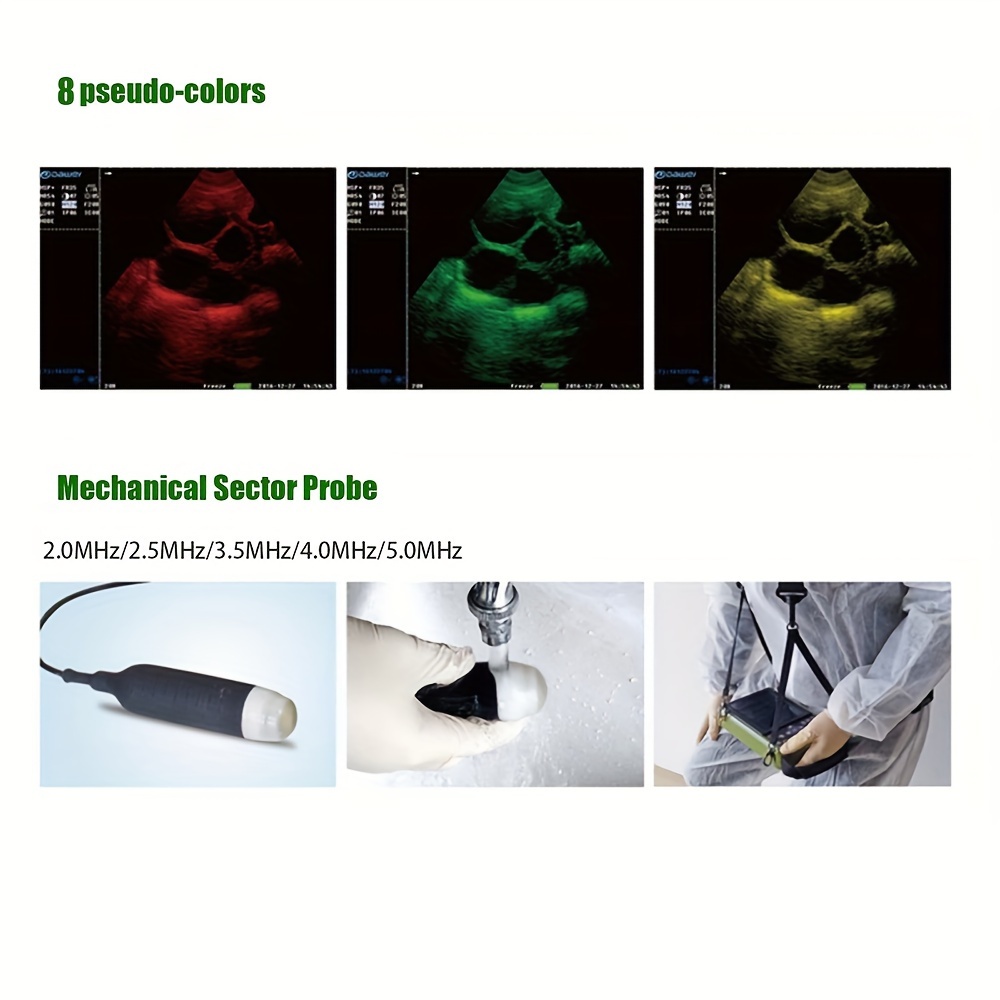

DAWEI-S0 Is A Portable Veterinary Ultrasound (B-ultrasound) Diagnostic Instrument. Its Superior Product Performance And Ergonomic Handheld Design Bring More Convenience To Users During Testing.